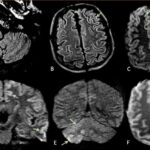

COVID-19 Inflicts Damage on Key Brain ‘Control Center,’ Revealed by Ultra-High-Resolution MRI Scans

A groundbreaking study has revealed a devastating consequence of COVID-19: severe damage to a critical brain control center. Ultra-powerful MRI scans have uncovered that the virus can target the brainstem, a vital region responsible for regulating essential bodily functions. This shocking discovery sheds light on the long-lasting symptoms experienced by many COVID survivors and … [Read more...] about COVID-19 Inflicts Damage on Key Brain ‘Control Center,’ Revealed by Ultra-High-Resolution MRI Scans